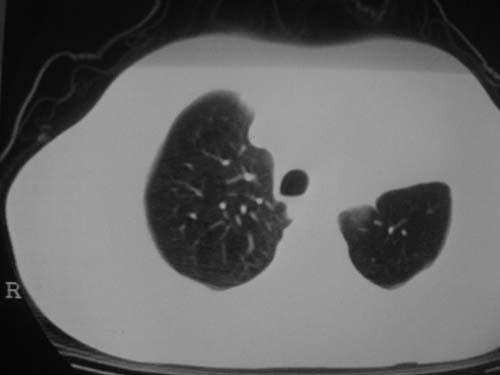

男性39岁,干咳一个月,最近胸憋气短,自己感觉发烧出汗,要求拍ct

图像质量较差请多包含,考虑肺癌,肺结核不除外,大家是否同意这种看法,请各位老师指教

左肺上叶中央型肺癌并阻塞性肺不张。

考虑:左肺上叶中央型肺癌并阻塞性肺不张。左肺下叶囊肿或支扩。

1.左侧肺癌伴阻塞性肺炎,纵隔转移。2.左下肺大泡。3.左下肺感染

纵隔淋吧结肿大

心包积液

双侧胸膜增厚

左肺上叶中央型肺癌并阻塞性肺不张。左下转移,支扩!

左肺上叶中央型肺癌并阻塞性肺不张,纵隔淋巴结转移。